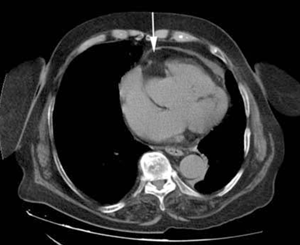

Se solicitó ecocardiografía transtorácica que mostró: fracción de eyección del ventrículo izquierdo (FEVI) 55%, ventrículo izquierdo con hipertrofia leve, hipoquinesia biventricular difusa, dilatación leve de aorta ascendente, aurícula izquierda moderadamente dilatada, engrosamiento pericárdico con probable derrame y colapso parcial de la aurícula derecha. Se solicitó tomografía de tórax (TC) sin contraste (figuras 1 y 2) que mostró una imagen típica de lipoma pericárdico, de 48 por 33 mm, que provocaba colapso de la aurícula derecha, considerándose la causa del taponamiento a baja presión. La angiografía coronaria no evidenció lesiones estenóticas significativas.

Figura 1: Tomografía de tórax sin contraste que muestra lipoma con obstrucción auricular derecha.